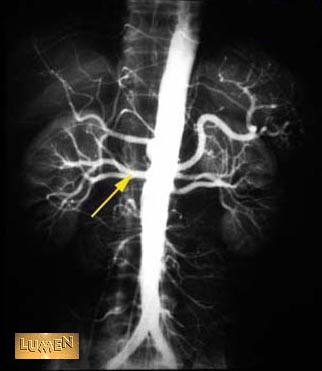

Renal artery.